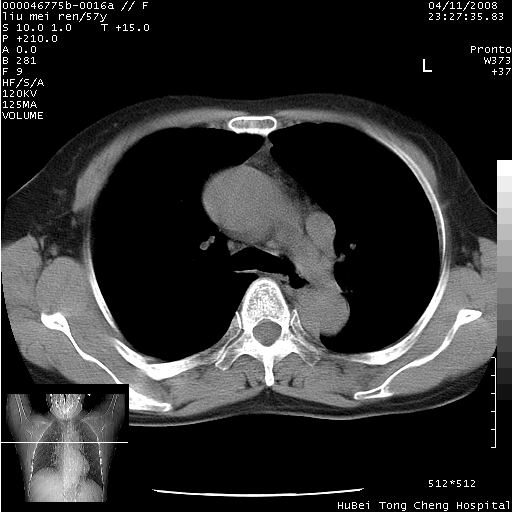

标题: CT12948:鉴赏一下——上腔静脉变异(CT平扫表现)。

患者 女,57岁。因车祸受伤,其家属要求行“全身ct检查”。平素健康。

胸部ct轴位平扫(层厚10mm,螺距1.5,重建间隔10mm),图像如下:

左位上腔静脉,先天变异。

上腔静脉变异,增强检查更全面一些。